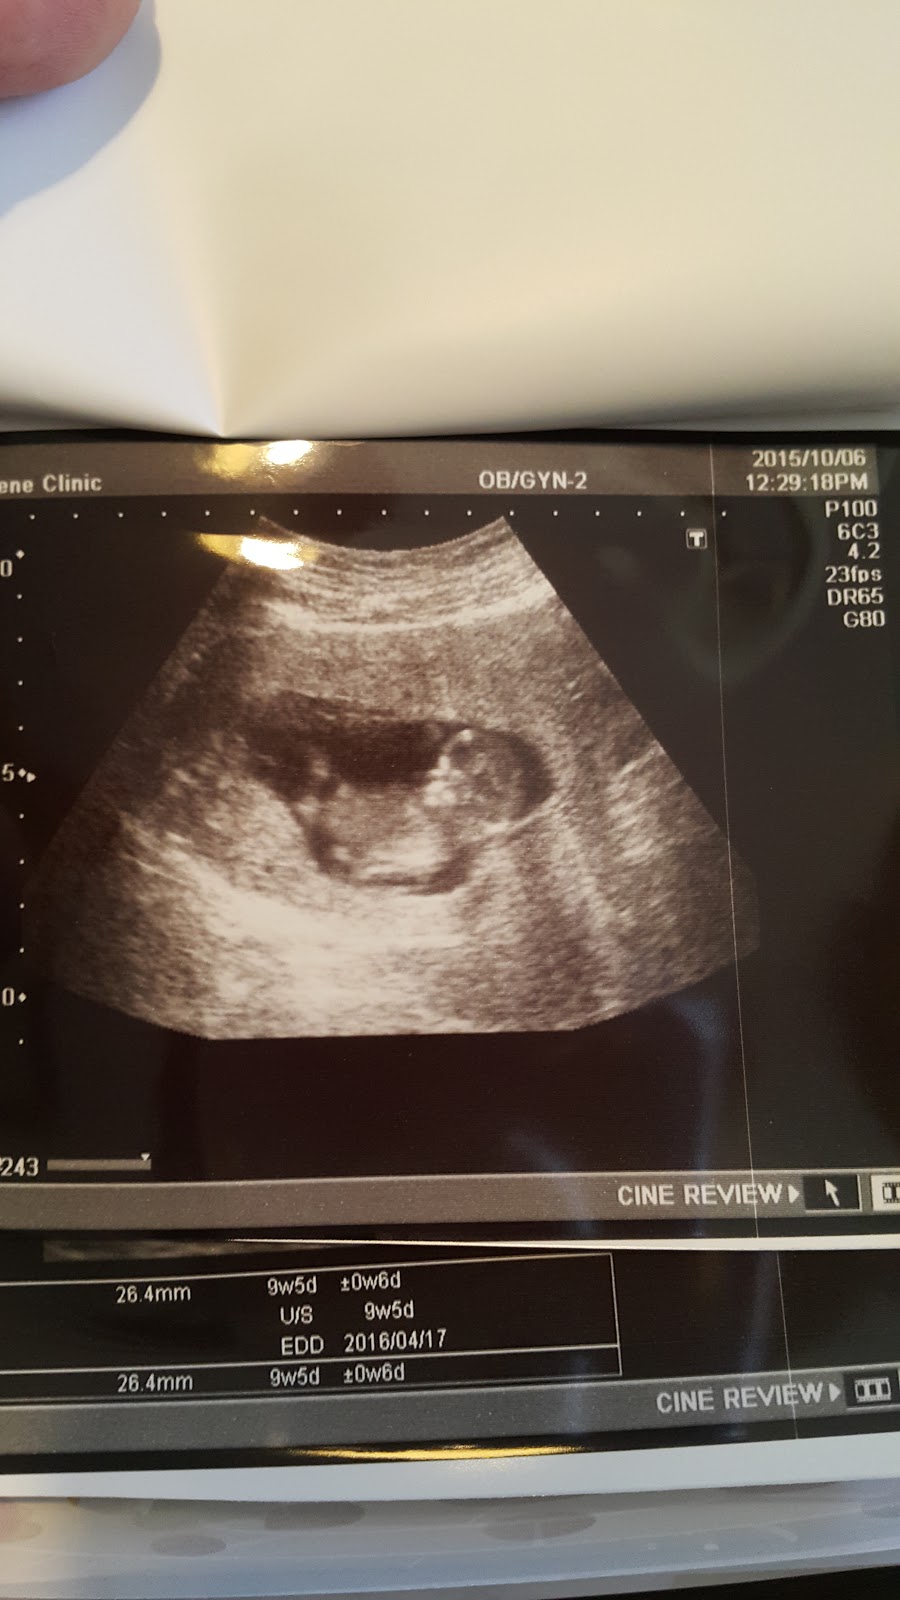

有時候認真把超音波照片拍下來與寫文章,除了記錄也是保存超音波照片的好方法吧!

接近中午,終於輪到我,醫生熱情的打招呼真的讓我安心不少,先是看了報告,報告一切正常,然後按例先照了超音波,寶寶真的有在好好長大!

這次看到更清楚的模樣了,手腳也很清楚,還看到寶寶在動,醫生說是個活潑的寶寶,看他在肚子裡動來動去的模樣,真的可愛極了!